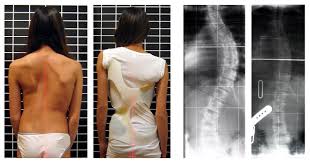

Behandeling van Rugklachten bij Scoliose: Tips en Advies

Scoliose is een aandoening waarbij de wervelkolom zijwaarts buigt, waardoor een S- of C-vormige kromming ontstaat. Deze abnormale kromming kan leiden tot rugklachten en andere gezondheidsproblemen. Scoliose kan op elke leeftijd voorkomen, maar wordt meestal vastgesteld bij kinderen in de groeifase. Een van de meest voorkomende symptomen van scoliose is rugpijn. Deze pijn kan variëren […]

Signaleren van Scoliose Symptomen: Belangrijke Kenmerken om op te Letten

Scoliose Symptomen: Herken de Signalen van deze Rugaandoening Scoliose is een aandoening waarbij de wervelkolom zijwaarts buigt, waardoor een S- of C-vormige kromming ontstaat. Het is belangrijk om de symptomen van scoliose te herkennen, zodat de aandoening tijdig kan worden vastgesteld en behandeld. Hier zijn enkele veelvoorkomende symptomen om op te letten: Rugpijn: Mensen met […]

Scoliose is een aandoening waarbij de wervelkolom zijwaarts buigt, wat kan leiden tot rugpijn en ongemak. Deze kromming kan mild zijn en weinig symptomen veroorzaken, of ernstiger worden en leiden tot meer ernstige complicaties. Rugpijn door scoliose is een veelvoorkomend probleem dat mensen van alle leeftijden treft. De exacte oorzaak van scoliose is vaak onbekend […]

Artikel: Rugpijn en Scoliose Rugpijn is een veelvoorkomende aandoening die mensen van alle leeftijden treft. Een specifieke vorm van rugpijn is scoliose, een aandoening waarbij de wervelkolom zijwaarts buigt, waardoor een ‘S’- of ‘C’-vorm ontstaat. Scoliose kan variëren in ernst en kan leiden tot rugpijn, vermoeidheid en zelfs ademhalingsproblemen als de kromming van de wervelkolom […]